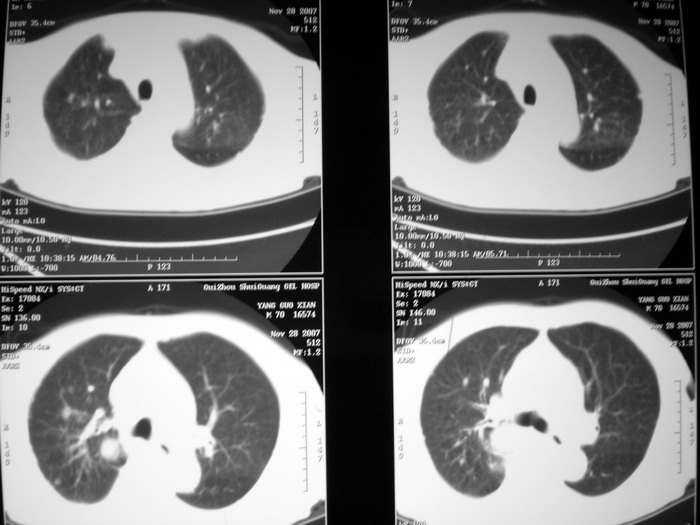

m、70y,反复咳嗽2月。请各位同仁给定位1、(肺?,纵隔?)2、定性。感谢!!

右后纵隔良性占位性病变,神经原性肿瘤可能性大,就其形态看,高密度囊肿待排,建议mri检查。

右下肺纵隔旁较大 均匀密度肿块,部分边缘植入纵隔,气管明显受压 变形。支持:后纵隔肿瘤!首选:神经源性!不支持肺内肿瘤原因:1 肿瘤位于下叶支气管及背段支气管开口区,但未侵犯支气管,只是受压表现。2 纵隔内未见肿大淋巴结。3 肺内未见阻塞性肺炎。

支持后纵隔肿瘤,病灶大体呈“滴状”与支气管关系密切,考虑:1.高密度支气管囊肿,2.神经纤维瘤。增强有鉴别意义。